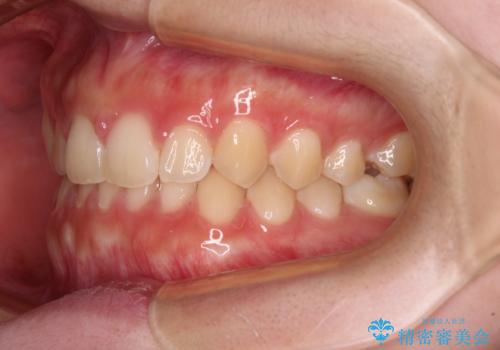

前歯のすきっ歯を治したい インビザラインによる矯正治療

- 上顎前歯の隙間を気にして来院された患者様です。

目立たない装置を希望とのことで、インビザラインを用いて矯正治療を行うこととしました。

一度インビザラインのマウスピースセットをお渡しすると1年以上来院されず、マウスピースを破損したり紛失したりすると来院されるというのんびりとしたペースで治療を行ったため、4年間という長期にわたる治療となりました。

最終的には隙間は全て閉じ、綺麗な仕上がりとなりました。